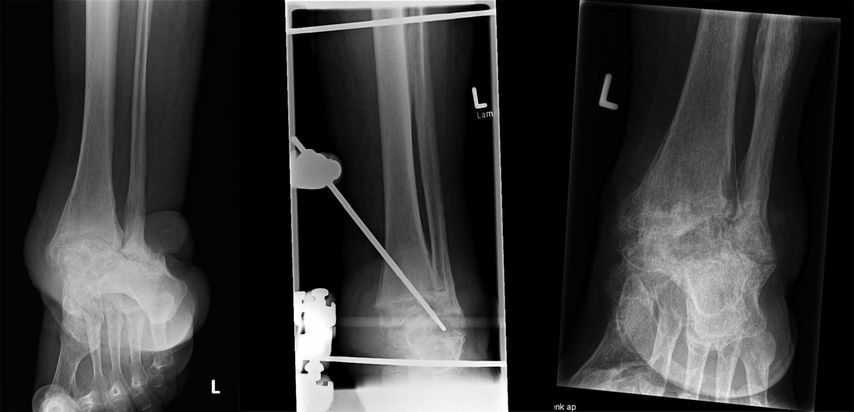

Das Skelett kann nach einem adäquaten Trauma atrophisch (Sanders-Typ 1) oder pseudarthrotisch (Mittelfußfrakturen) sein. Insuffizienzfrakturen betreffen häufig den Kalkaneus (Sanders-Typ 5) oder die Metatarsalmetaphyse (Sanders-Typ 2); Kompressionsfrakturen des Talus (Sanders-Typ 3, 4) ähneln einer avaskulären Nekrose im Spätstadium. Darüber hinaus können ein Luxationstyp (vor allem Sanders-Typ 2 und 3), ein klassischer Frakturtyp („Bag of Bones“) und eine Vielzahl von Mischtypen beobachtet werden.

Eine stabile Fixierung des Fußes wird durch zwei weitere „full pins“ erreicht, von denen einer durch den Tuber calcanei und der zweite durch die distalen Mittelfußknochen (retrokapital) geführt wird, wo diese Knochen normalerweise in einer Ebene liegen. Während das Einsetzen des Fersenbein-Pins sicher und einfach ist, kann das Bohren des Mittelfuß-Pins durch alle 5 Knochen technisch anspruchsvoll sein. Im Gegenzug sorgen mehrere Corticales für eine ausgezeichnete Stabilität, sodass die Fixierung des ersten Strahls zusammen mit zwei kleinen Mittelfußknochen eine zufriedenstellende Fixierung bietet; ein oder zwei zusätzliche Knochen verbessern die Steifigkeit. Zwei Stangen, in der Regel 300mm lang, sind an den beiden Fußstiften befestigt. Ein Verbindungssteg unterhalb der Ferse ergibt zusammen mit den Stegen an beiden Seiten des Fußes die Form eines „U“. Die Verbindung der 4Tibiastäbe mit dem Pedal-U-Rahmen führt schließlich zu einer Box-Konfiguration, die in allen geometrischen Ebenen den gleichen Widerstand gegen Verformung bietet.

Durch die Verwendung desselben Satzes von Stiften, Stäben und Klammern bietet das Box-Frame-Design Anpassungsmöglichkeiten für die Rekonstruktion des Mittelfußes oder des Knöchels. Bei einem Charcot-Sprunggelenk ist der Fuß zunächst in seinem U-förmigen Rahmen fixiert. Gegenläufige Bewegungen der Stäbe auf beiden Seiten des Fußes ermöglichen die Supination oder Pronation des Vorfußes im Verhältnis zum Rückfuß. Danach wird der Fuß in die korrigierte Position manövriert. Außerdem kann eine Kompression erreicht werden, indem der Fuß-U-Rahmen proximal an den 4 Tibiastäben entlang nach proximal geschoben wird, bis eine (leichte) Biegung der Pedalstifte nach oben festgestellt wird. Die Kompression darf nicht übertrieben werden, um eine reversible, elastische Verformung der Pins, nicht aber eine irreversible plastische Verformung zu erreichen. Federstahl mit einer hohen Elastizitätsgrenze ist daher das optimale Pinmaterial.

Wenn das Lisfranc- oder das Chopart-Gelenk betroffen sind, sollte der Chirurg zunächst den Rückfuß stabilisieren und dann den Vorfuß ausrichten. Bei intaktem Sprunggelenk und Subtalargelenk wird der kalkaneare Pin an den beiden dorsalen Tibiastäben befestigt. Die Equinusdeformität im Sprunggelenk, die häufig mit der Charcot-Krankheit des Mittelfußes einhergeht, kann nun korrigiert werden, indem der Kalkaneus-Pin nach distal gezogen wird, mit oder ohne Verlängerung der Achillessehne, was zu einer Dorsalextension im Sprunggelenk führt. Auch hier gilt es, eine plastische Verformung des Stifts zu vermeiden. Der nächste Schritt ist das Bohren des Mittelfuß-Pins, der an den beiden ventralen Tibiastäben befestigt wird. Die beiden parallel zum Fuß verlaufenden Stäbe werden an den Tibiastäben befestigt. Schließlich wird der Stab unterhalb der Ferse mit den Fußstäben verbunden, sodass wieder die Form eines „U“ entsteht. Eine Kompression ist entlang der Fußschienen möglich, zusätzliche Apex-Pins mit distalem Gewinde, die die Fusionszone kreuzen, sind hilfreich, um die Kompressionskräfte zu bündeln, analog zum sogenannten Beaming-Konzept, und um eine Fragmenttranslation zu vermeiden.

Ein weiterer Nachteil ist der große Abstand zwischen der Fixierung in der proximalen Tibia und dem Fuß. Wenn das Sprunggelenk oder das subtalare Gelenk rekonstruiert werden muss, kann es schwierig sein, die Translationsbewegung an der Fragmentstelle zu eliminieren. Da die Scherkräfte, die mit der Fragmenttranslation einhergehen, der Frakturheilung abträglich sind, sind zusätzliche Fixierungselemente erforderlich, um eine angemessene Stabilität zu erreichen. Zu diesem Zweck können am Rahmen befestigte Apex-Pins (mit distalem Gewinde) mit oder ohne Verbindung zum Rahmen verwendet werden.